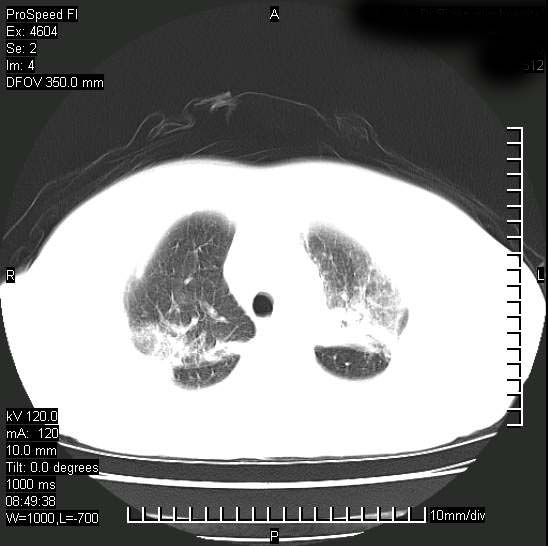

标题: CT15528:女性,79岁,近几日晚上高热,39度,仍咳少量血

十几年前曾患肺结核,一周前突咳血约100ml,中性粒细胞稍高,诊断两上肺陈旧结核,下肺炎症,给予抗炎治疗,近几日晚上高热,39度,仍咳少量血,4天前ct及今天ct上传。

[face=黑体]8月30日[/face]